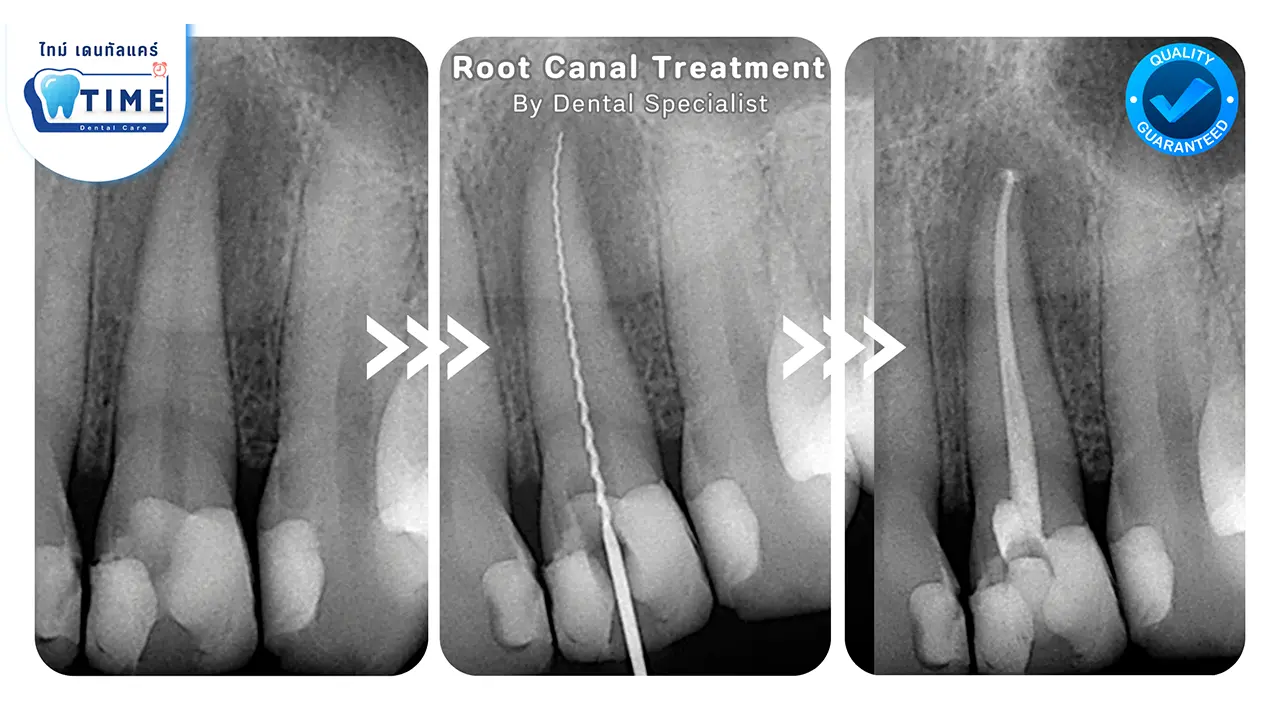

Root Canal Treatment

การรักษาคลองรากฟัน

• การวินิจฉัย: หมอฟันจะตรวจสอบอาการของคุณ โดยมักใช้เอ็กซ์เรย์

• การทำความสะอาด: จะมีการนำเนื้อเยื่อที่ติดเชื้อออกและทำความสะอาดฟัน

• การอุดฟัน: ฟันจะถูกอุดด้วยวัสดุที่ปลอดภัย